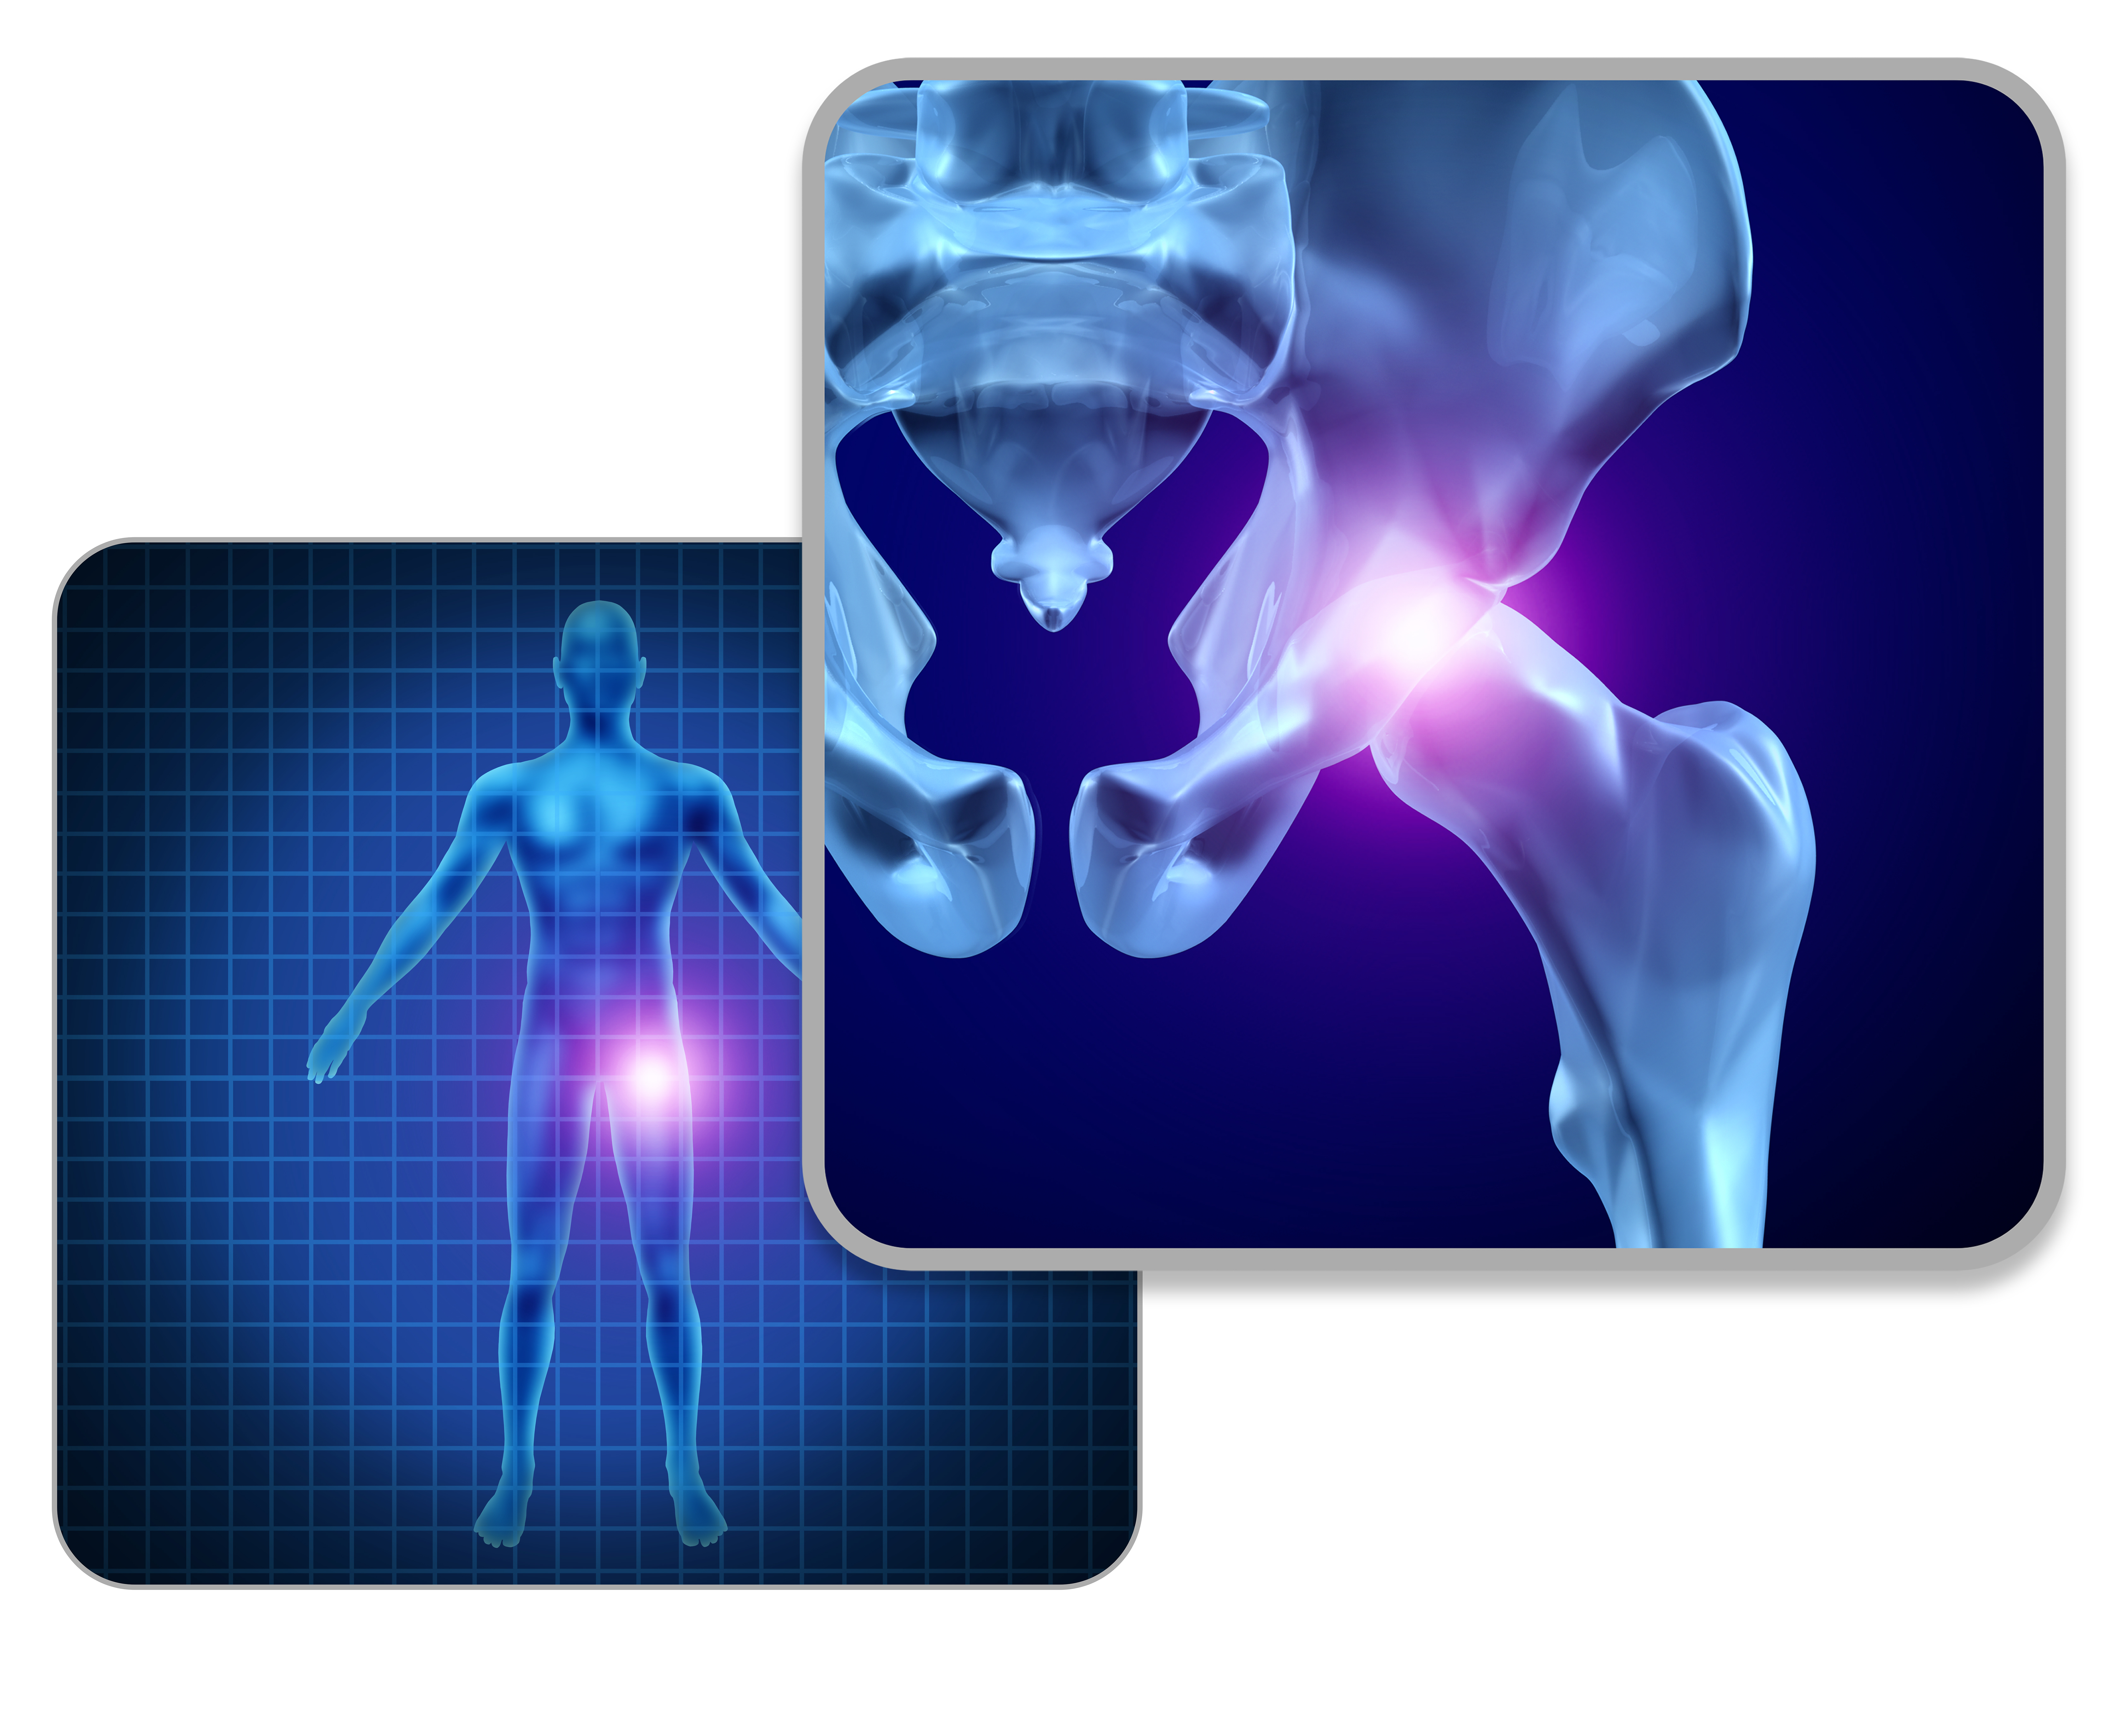

髋关节的X线解剖及应用技巧,最全总结!

目前,一张标准的X片图像仍然能为我们的临床诊断与决策提供重要的依据。为了全面评估髋部疼痛患者的病情,X线片图像仍然是有效手段。